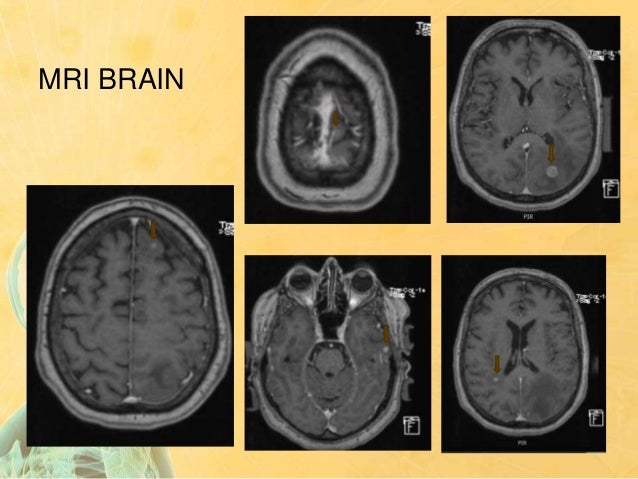

View Hippocampal Sparing Whole Brain Radiotherapy Pics. Improved plan quality with automated radiotherapy planning for whole brain with hippocampus sparing: Hippocampal sparing whole brain radiotherapy vs conventional whole brain radiotherapy in patients with brain metastases.

Whole brain radiotherapy with hippocampal avoidance and simultaneously integrated brain metastases boost:

Additionally, simultaneous integrated boost (sib) on individual metastases may further improve the outcome. Further trials are needed to evaluate the use of neurocognitive protective agents and hippocampal sparing with wbrt. Considerations from the uk hippo trial qa programme. The british journal of radiology, 2017.